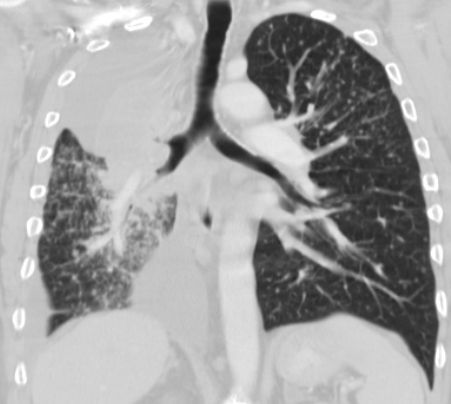

CT

Zentrales kleinzelliges Karzinom rechts. Typisch für Kleinzeller ist die fließende Ausbreitung im Mediastinum.

Kleinzelliges Karzinom des rechten Hauptbronchus mit Occlusion des Oberlappenbronchus T3 N2 M1 bra, pul,adren